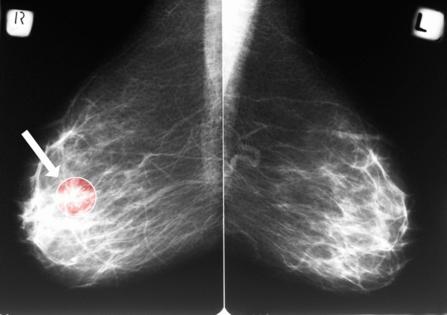

Routine mammograms are best known as a front-line tool for detecting breast cancer. But new research suggests the same X-ray images may also offer an early warning sign for cardiovascular disease — the leading cause of death among women.

A study presented at a Dec. 3 Radiological Society of North America meeting found that calcium deposits visible in the arteries of the breast can help predict a woman's future risk of heart attack, heart failure, stroke and death. The findings add to growing evidence that mammograms may hold untapped value beyond cancer screening.

The condition that mammograms can detect — and act as an early warning of heart problems down the road — is called breast arterial calcification, said Matthew Nudy, an assistant professor of medicine and public health sciences at Penn State College of Medicine who presented the findings.

Breast arterial calcification, or BAC, is relatively common, appearing in an estimated 15% to 25% of screening mammograms. Yet it is not routinely reported.

Despite often being discernible on routine mammograms, radiologists do not typically report the presence of these calcifications "because there's no known association between this breast arterial calcification and breast cancer," Nudy said.

In the new Penn State study, researchers analyzed data from 10,348 women who had undergone at least two mammograms at a U.S. academic medical center, with an average of 4.1 years between scans. Using an artificial intelligence tool, the team measured the severity and progression of calcification in breast arteries over time.

They found that nearly 1 in 5 women had detectable vascular calcification at baseline. More importantly, the severity and progression of that calcification mattered. Women with worsening calcium buildup faced significantly higher risks of major cardiovascular events — up to double the risk for those with the most severe scores, Nudy explained.

Unlike coronary artery calcium scoring — a CT scan is sometimes ordered to assess heart disease risk — identifying BAC does not require additional testing, radiation or cost, Nudy pointed out.

Instead, the data already exist on routine mammograms performed for breast cancer screening.

In this study, researchers used AI to quantify calcification efficiently across thousands of images.